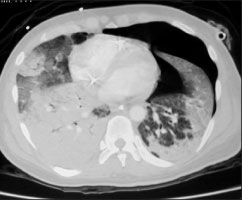

The patient was intubated in the emergency room to protect his airway. He underwent bronchoscopy with bronchoalveolar lavage on hospital day 2; all cultures, including those for bacteria, viruses, and mycobacteria, as well as those using acid-fast bacilli smear and silver stain, yielded negative results. Urinary Legionella antigen test results were also negative, as were multiple blood cultures. On hospital day 5, the patient's condition deteriorated, and a CT scan showed evidence of a left-sided spontaneous pneumothorax (Figure 2). A chest tube was inserted; however, the patient's oxygen requirements continued to increase and he required a fraction of inspired oxygen of 100% with the addition of positive end-expiratory pressure. His antibiotic regimen was broadened to include piperacillin/tazobactam, vancomycin, amphotericin B, isoniazid, rifampin, ethambutol, and pyrazinamide.

Figure 2. CT scan showing evidence of left-sided pneumothorax.